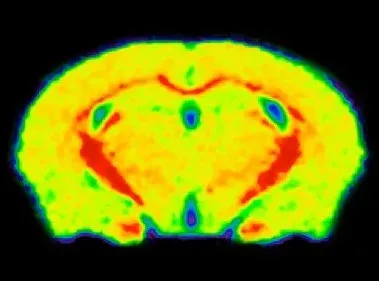

MTR map of a control mouse brain showing high (red) signal in the corpus callosum.

In vivo MRI Measures

Multi-modality brain imaging biomarkers are widely used in clinical trials of multiple sclerosis. MRI-derived measures of lesion volumes, gadolinium enhancement, lesion biophysical characteristics, and brain atrophy are effective biomarkers of disease progression and response to therapy.

Using whole-brain, high-resolution, anatomical MRI acquisition paired with advanced fully-automated image processing & analysis, we have shown:

- Reproducible magnetization transfer ratio (MTR) measures in the cuprizone model of MS, allowing for longitudinal monitoring of demyelination & remyelination